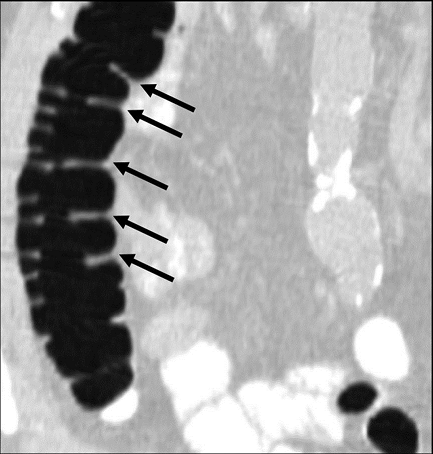

A single reviewer evaluated all data sets using a DICOM image viewer (OsiriX v4.0) for inclusion into this study. Inclusion criteria were: (1) adequate colonic distension and (2) presence of measurable folds. Having a minimum of at least five consecutive measurable haustral fold pairs in a given colonic segment was established as a marker of adequate bowel distention for optimal measurement of folds. Measurable folds were defined as folds that were not obscured or distorted by retained fluid, luminal collapse, tortuosity or diverticulosis. As haustral folds meet at the teniae coli, two of the three folds were each measured with the most dependent fold excluded; the most dependent folds were most often obscured by fluid if present (Figure 1A). Measurements of fold heights were made on 2D multiplanar reformations; the imaging plane demonstrating the folds in cross-section was established for optimal measurement of fold heights (Figure 1B). Due to the high frequency of tortuosity, suboptimal distention relative to other colonic segments, distortion of the folds and diverticulosis relative to other colonic segments, the sigmoid colon was not included in this study.

Figure 1B.Coronal reformat demonstrating adequately distended ascending colon with at least five non-dependent haustral folds (black arrows) clearly visualized. (Multiplanar CT Colonography, Haustral Fold Selection, Axial).